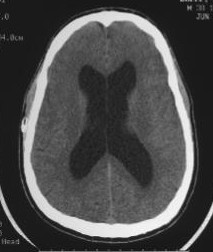

In February 2010, I was emergently revised and the new Low Profile Orbis Sigma (OSV-II) valve was implanted. Four months later I began to overdrain and experience "Slit Ventricles" according to CT images below. I questioned this new shunt's equivalence and flow rate to the standard Orbis Sigma valve. Based on my CT scan and complaints, I speculate this Low Pro valve had a 20% higher flow rate than specification.

CT Image 6-11-2010, 4 months post Low Profile OSV II valve (image/CD courtesy of Hoag Imaging Center)